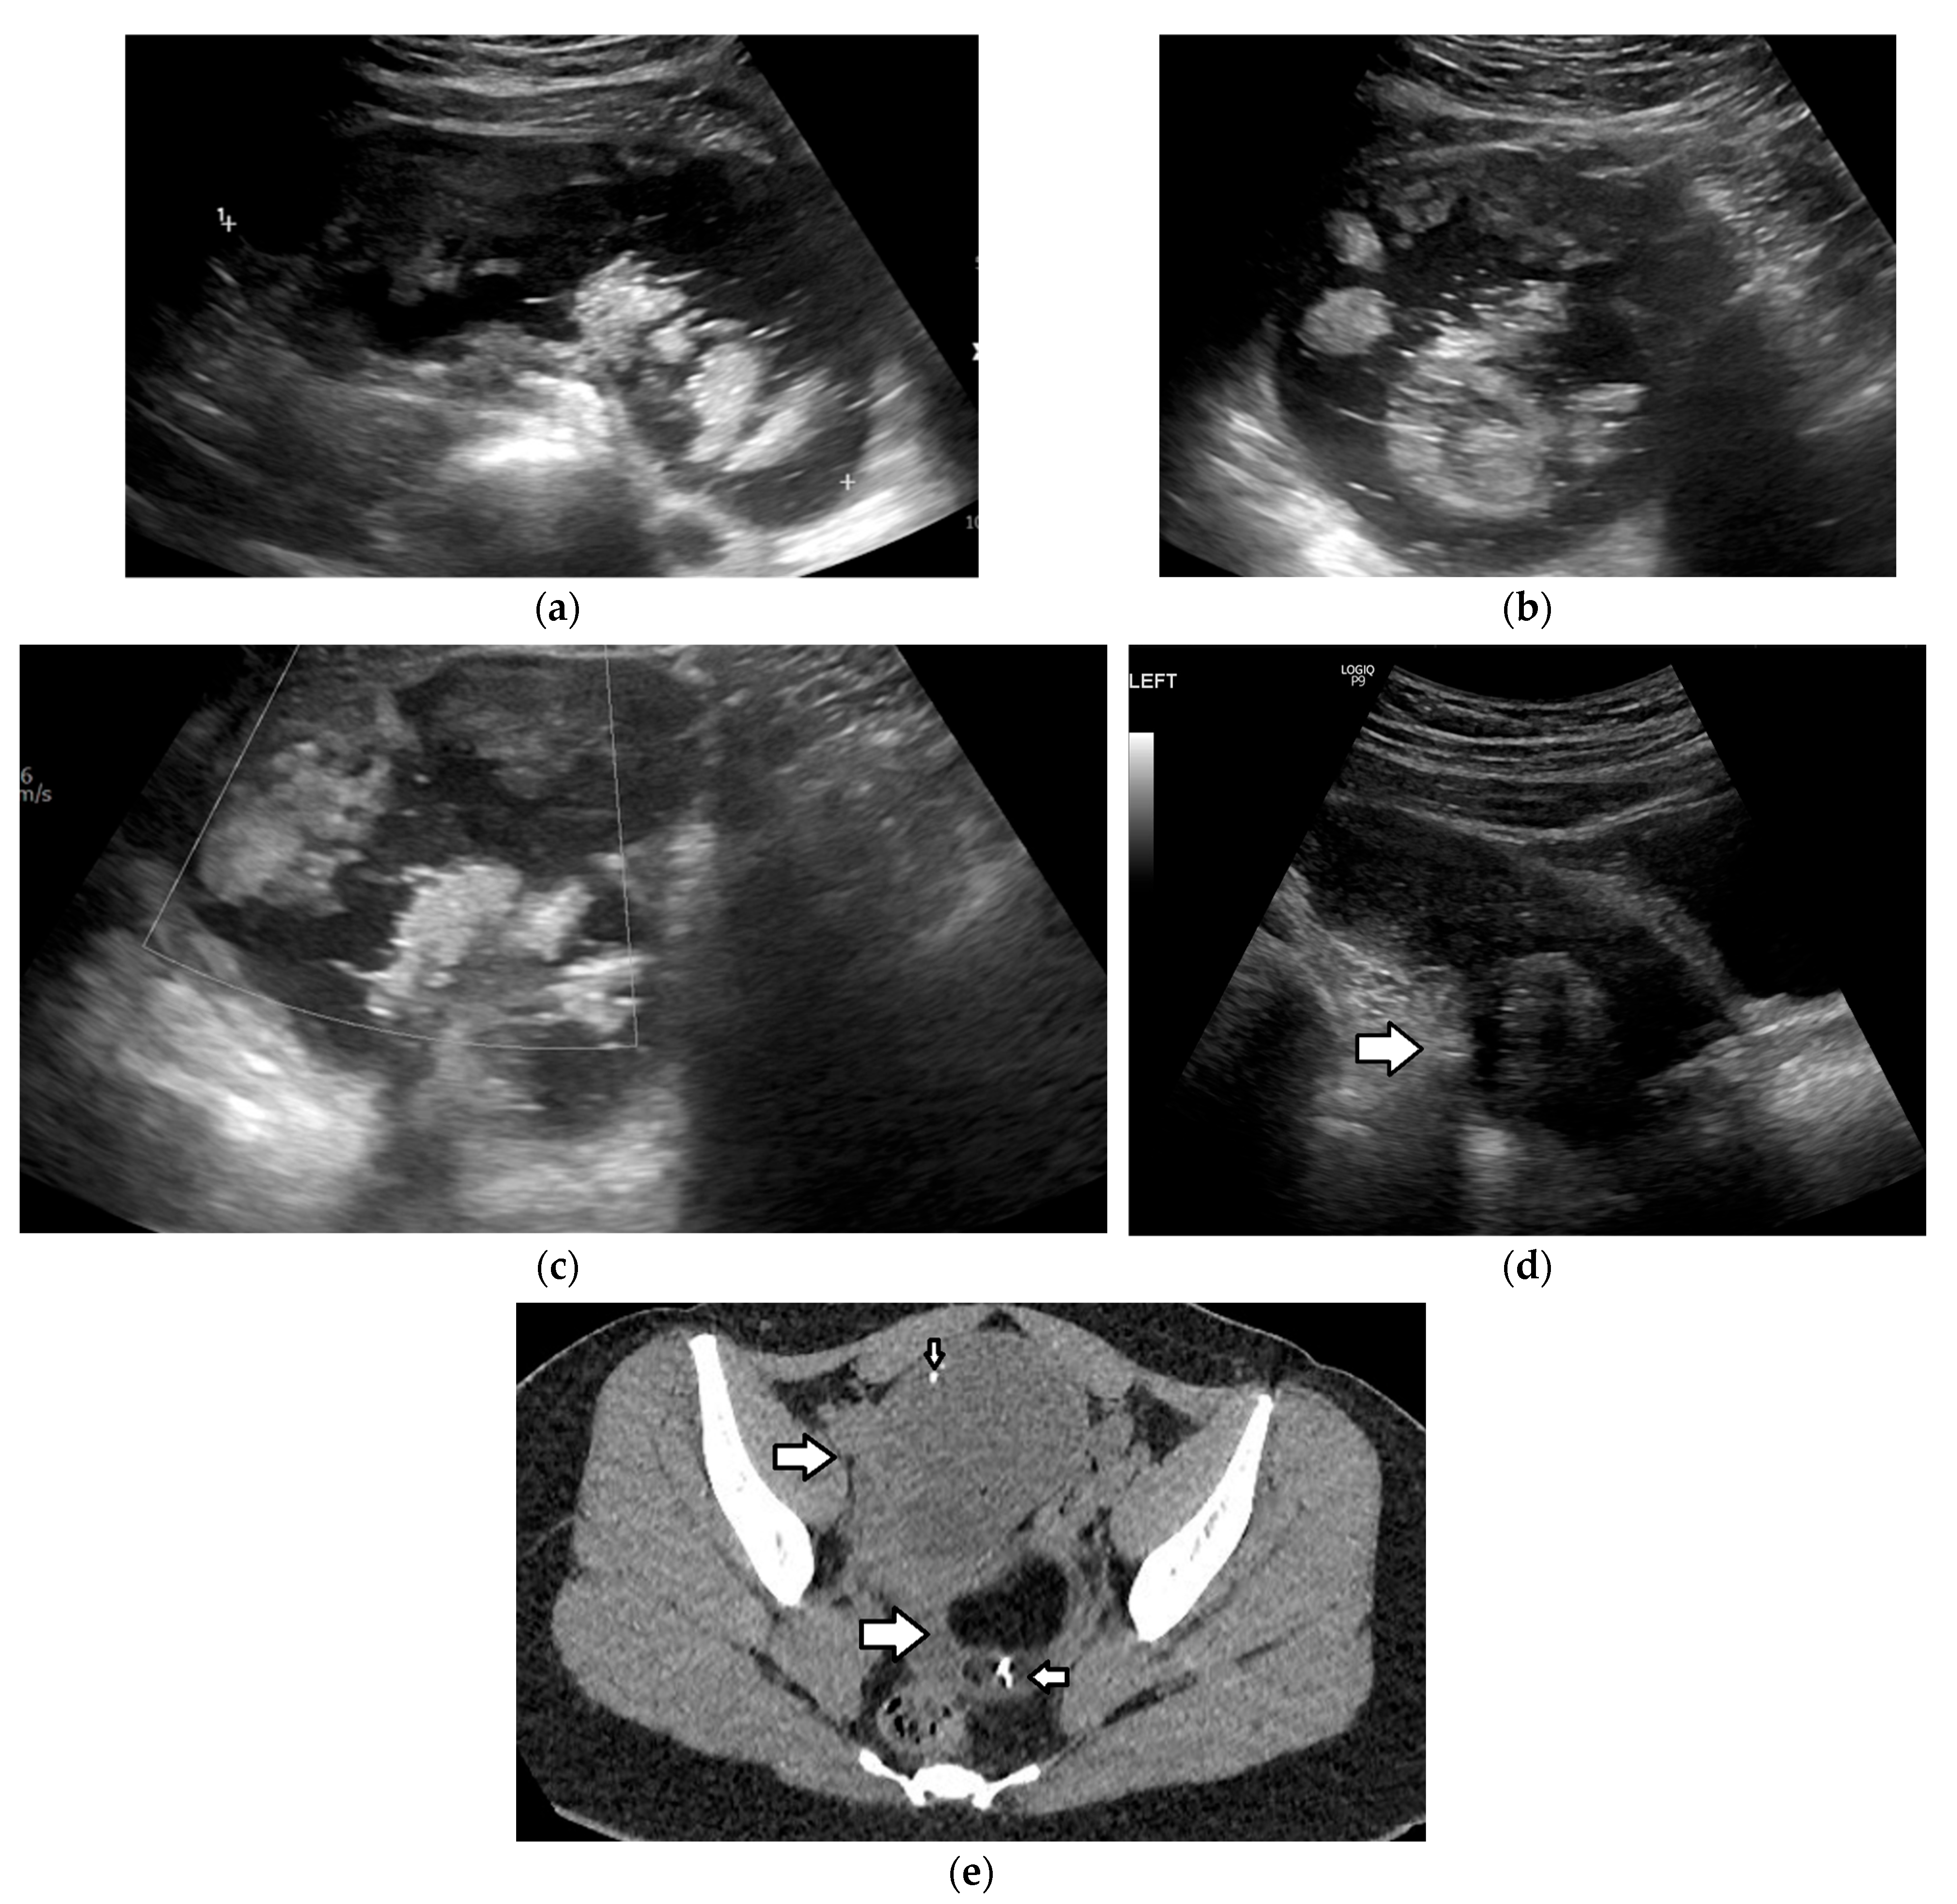

| Mature teratoma | most common benign ovarian tumor most common GCT mean age: first, second decades often asymptomatic bilateral: 10–25% 10% of MOGCTs, in contralateral ovary | benign complications: torsion, rupture, infection, malignant transformation (rare) | mean diameter: 6.5 cm US:

| |